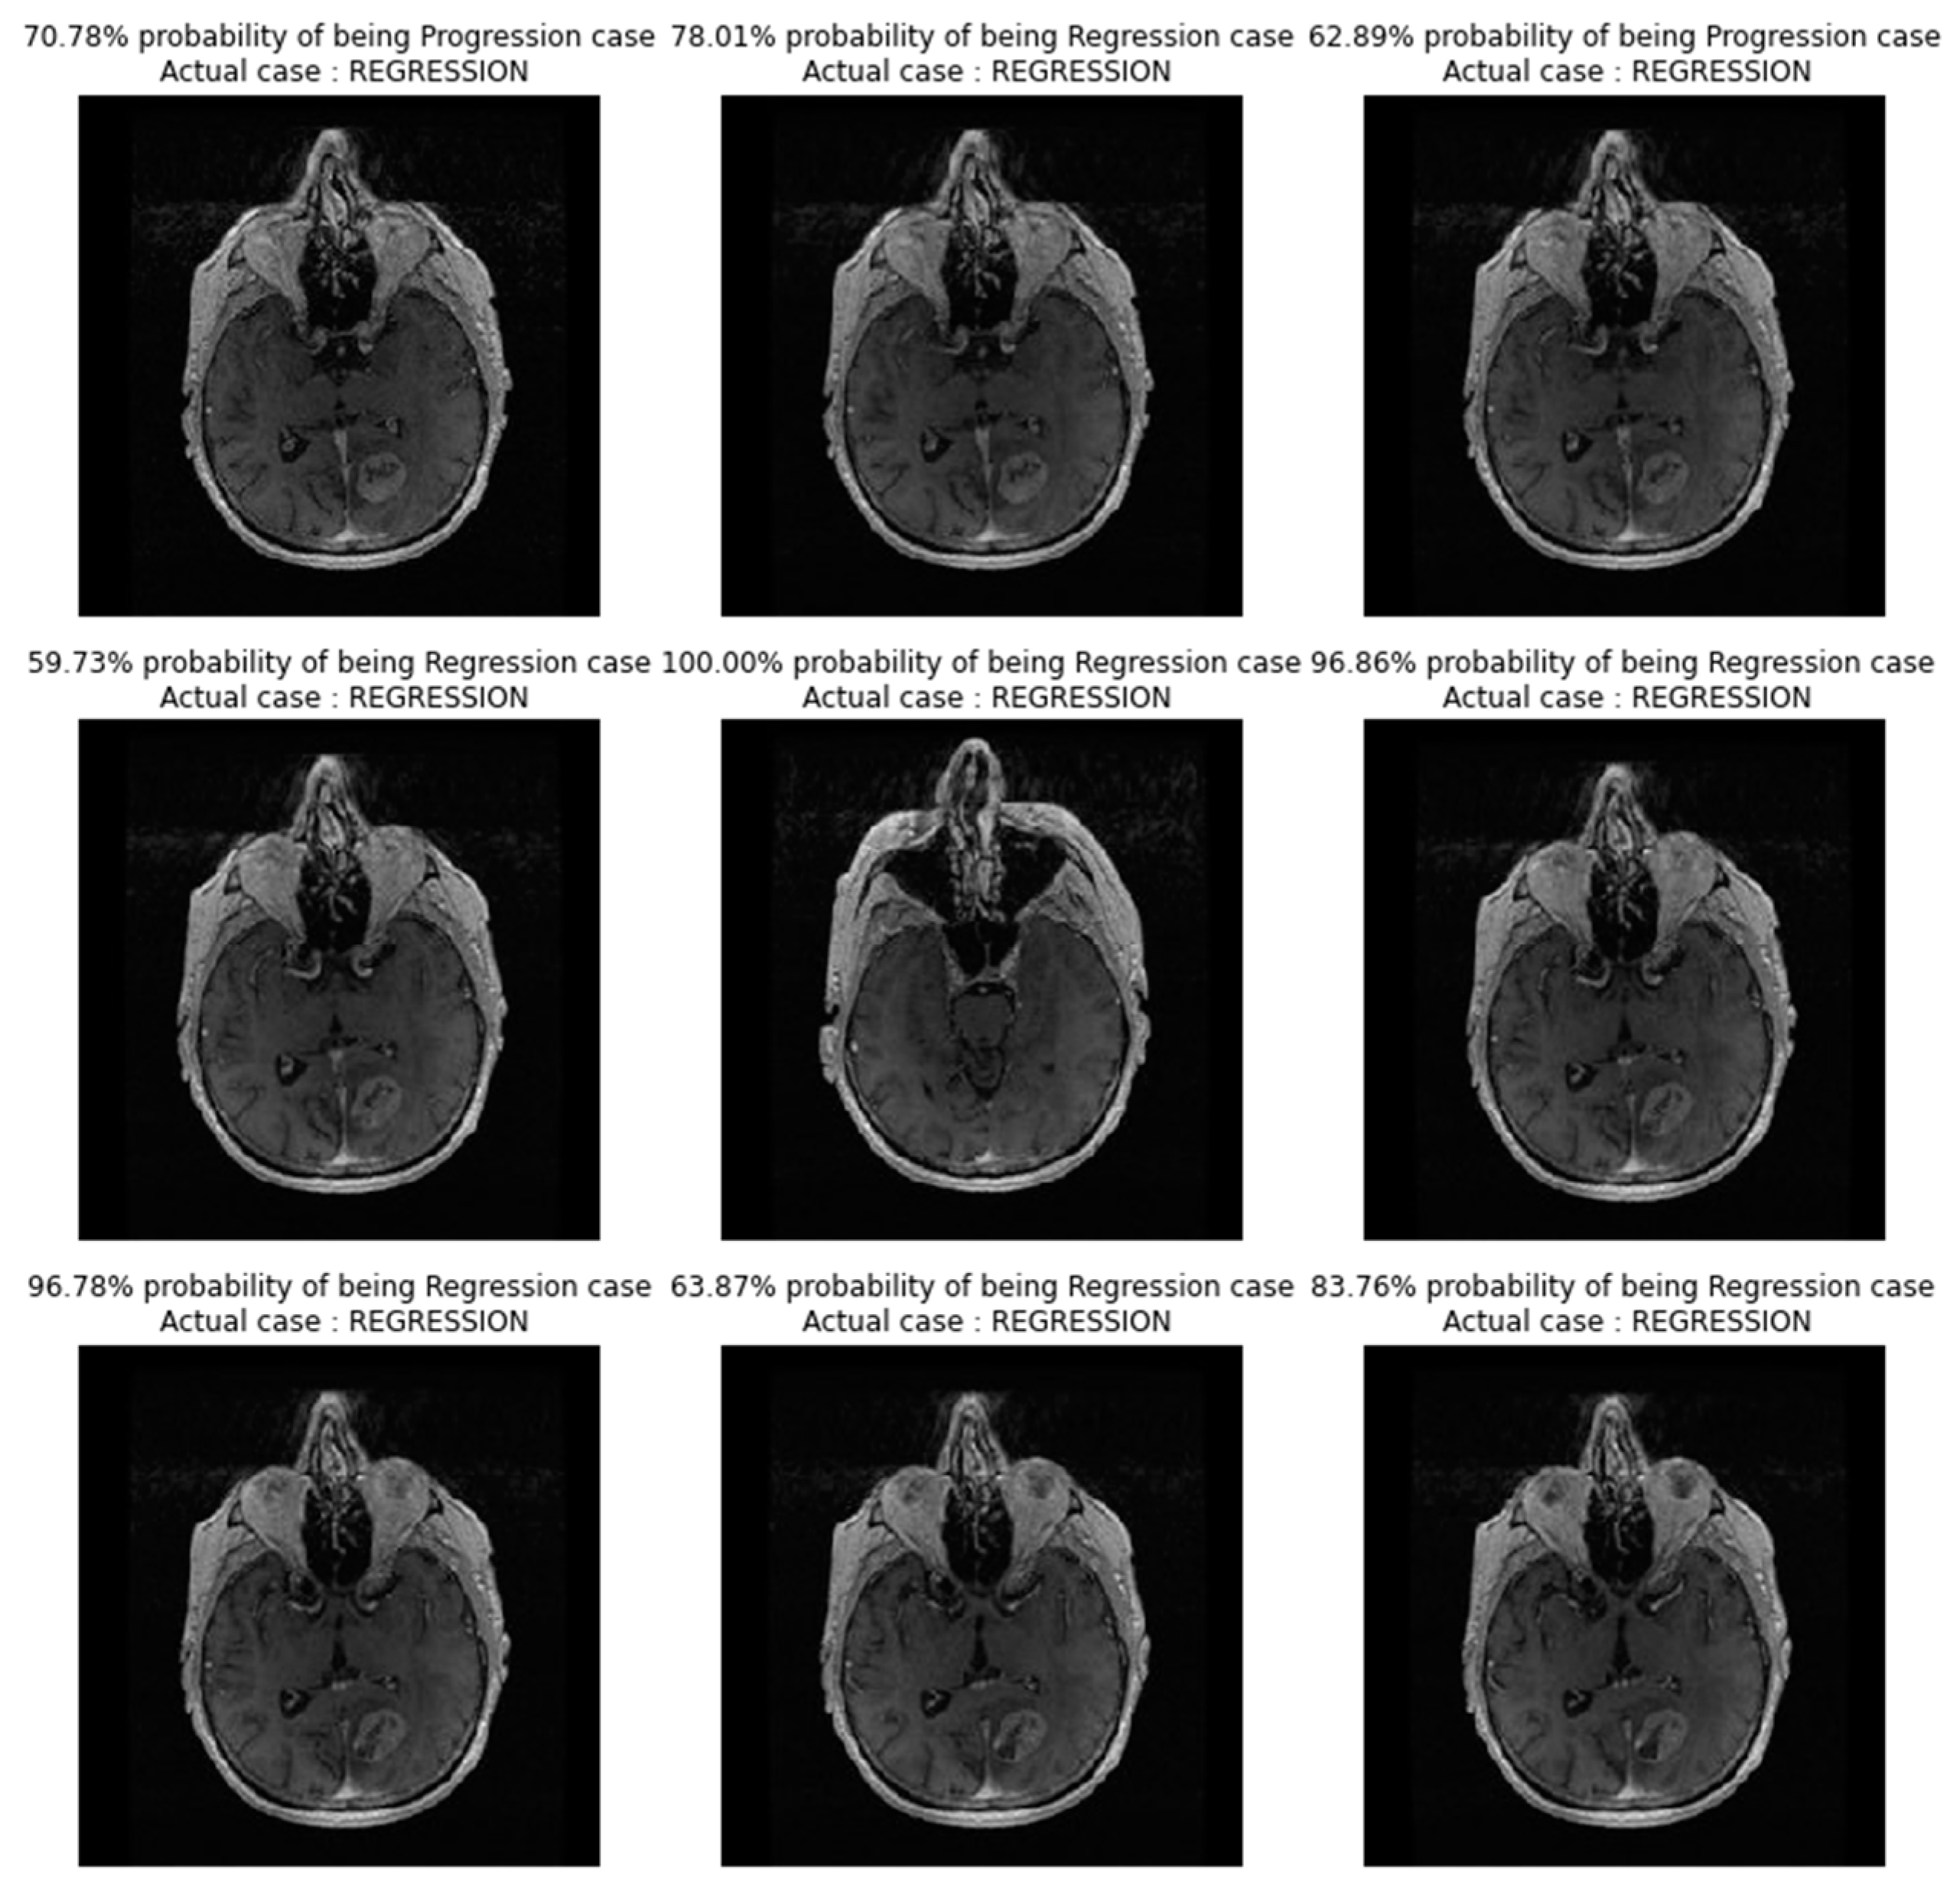

In Figure 4, images showing actual cases versus the predicted cases, with the probability of prediction, for the CNN_model from scratch on unseen images, are presented.

Figure 4. Images showing actual cases versus the predicted cases, with probability of prediction, for the CNN_model from scratch on unseen images.